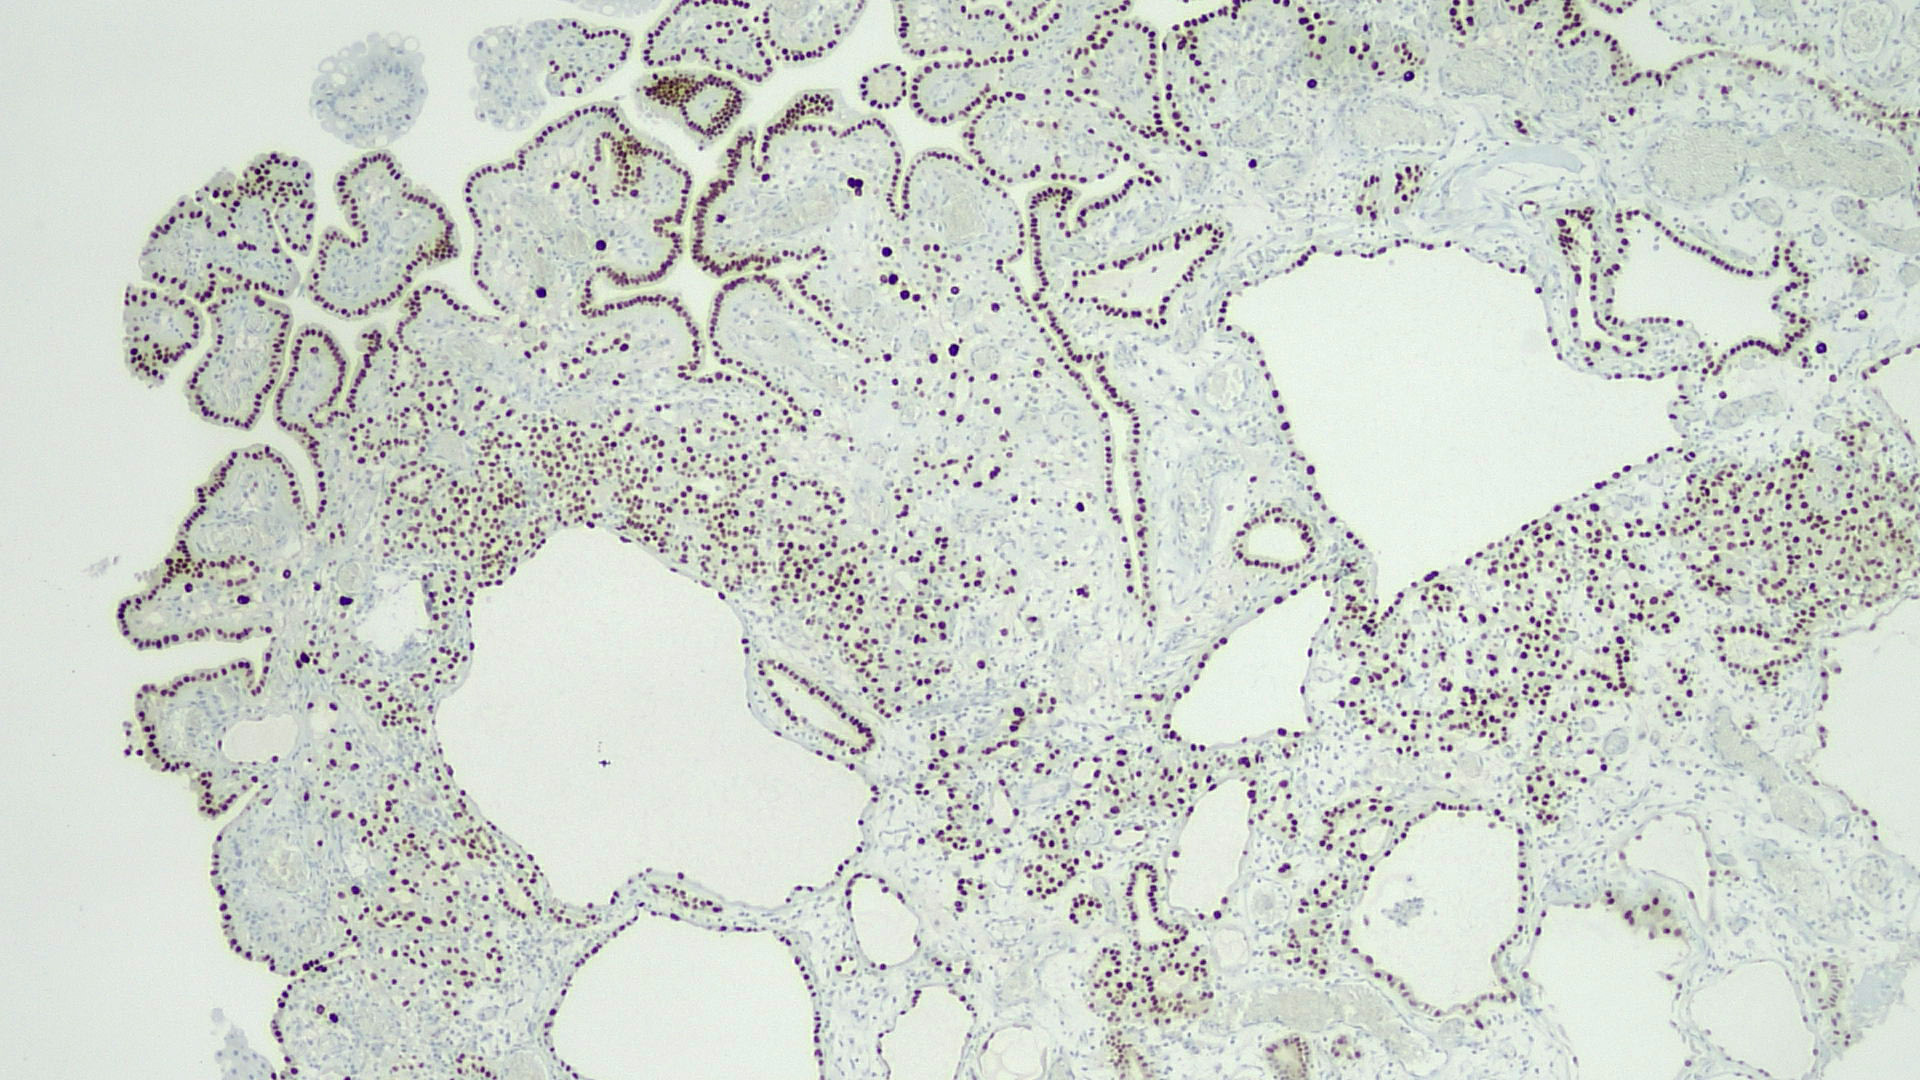

Microscopic (histologic) images

Positive stains

- PAX2, PAX8, AMACR, CD10, CK7 (Am J Surg Pathol 2014;38:1664)

- CK903, EMA, S100A1 (Ann Diagn Pathol 2013;17:41)

- Napsin A (Hum Pathol 2020;102:23)

- Weakly positive or negative for PSA and PSAP

- Very low Ki67 proliferation rate (< 5%) (Ann Diagn Pathol 2019;38:11)